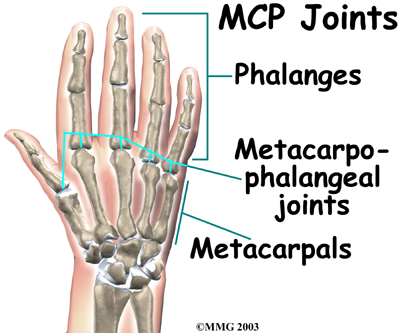

The main knuckle joints are formed by the connections of the phalanges to the metacarpals. These joints are called the (MCP joints). The MCP joints work like a hinge when you bend and straighten your fingers and thumb.

The three phalanges in each finger are separated by two joints, called interphalangeal joints (IP joints). The one closest to the MCP joint (knuckle) is called the proximal IP joint (PIP joint). The joint near the end of the finger is called the distal IP joint (DIP joint). The thumb only has one IP joint between the two thumb phalanges. The IP joints of the digits also work like hinges when you bend and straighten your fingers and thumb.